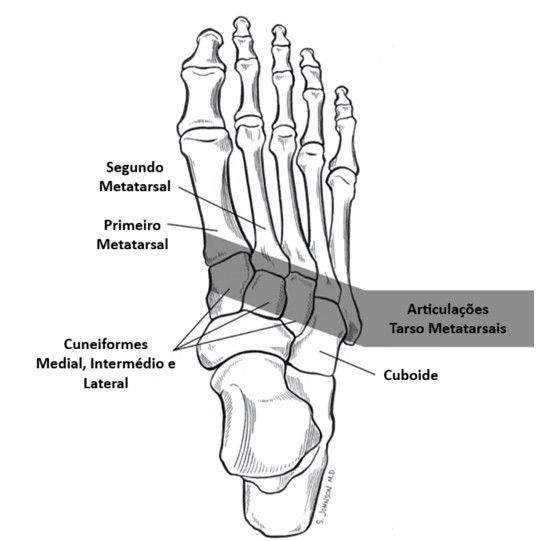

O que são as articulações tarso metatarsais e por que elas são tão importantes?

Imagine o seu pé como uma estrutura complexa, com muitos ossos e articulações trabalhando em harmonia. As articulações tarso metatarsais estão localizadas na parte central do seu pé, onde os ossos do "tarso" (uma região mais atrás, próxima ao tornozelo) se encontram com os "metatarsos" (os ossos longos que dão origem aos seus dedos).

Elas são como a "base móvel" do seu arco, essenciais para a flexibilidade e estabilidade do pé. A função dessas articulações é primordial:

- Absorção de Impacto: Amortecem o choque a cada passo que você dá.

- Flexibilidade: Permitem que o pé se adapte a diferentes tipos de terreno.

- Estabilidade: Mantêm a estrutura do pé firme durante o movimento.

- Propulsão: Ajudam a impulsionar o corpo para frente ao caminhar ou correr.

Quando essas articulações estão saudáveis, você nem percebe o trabalho delas. Mas, quando algo não vai bem, a dor pode ser intensa e muito limitante.